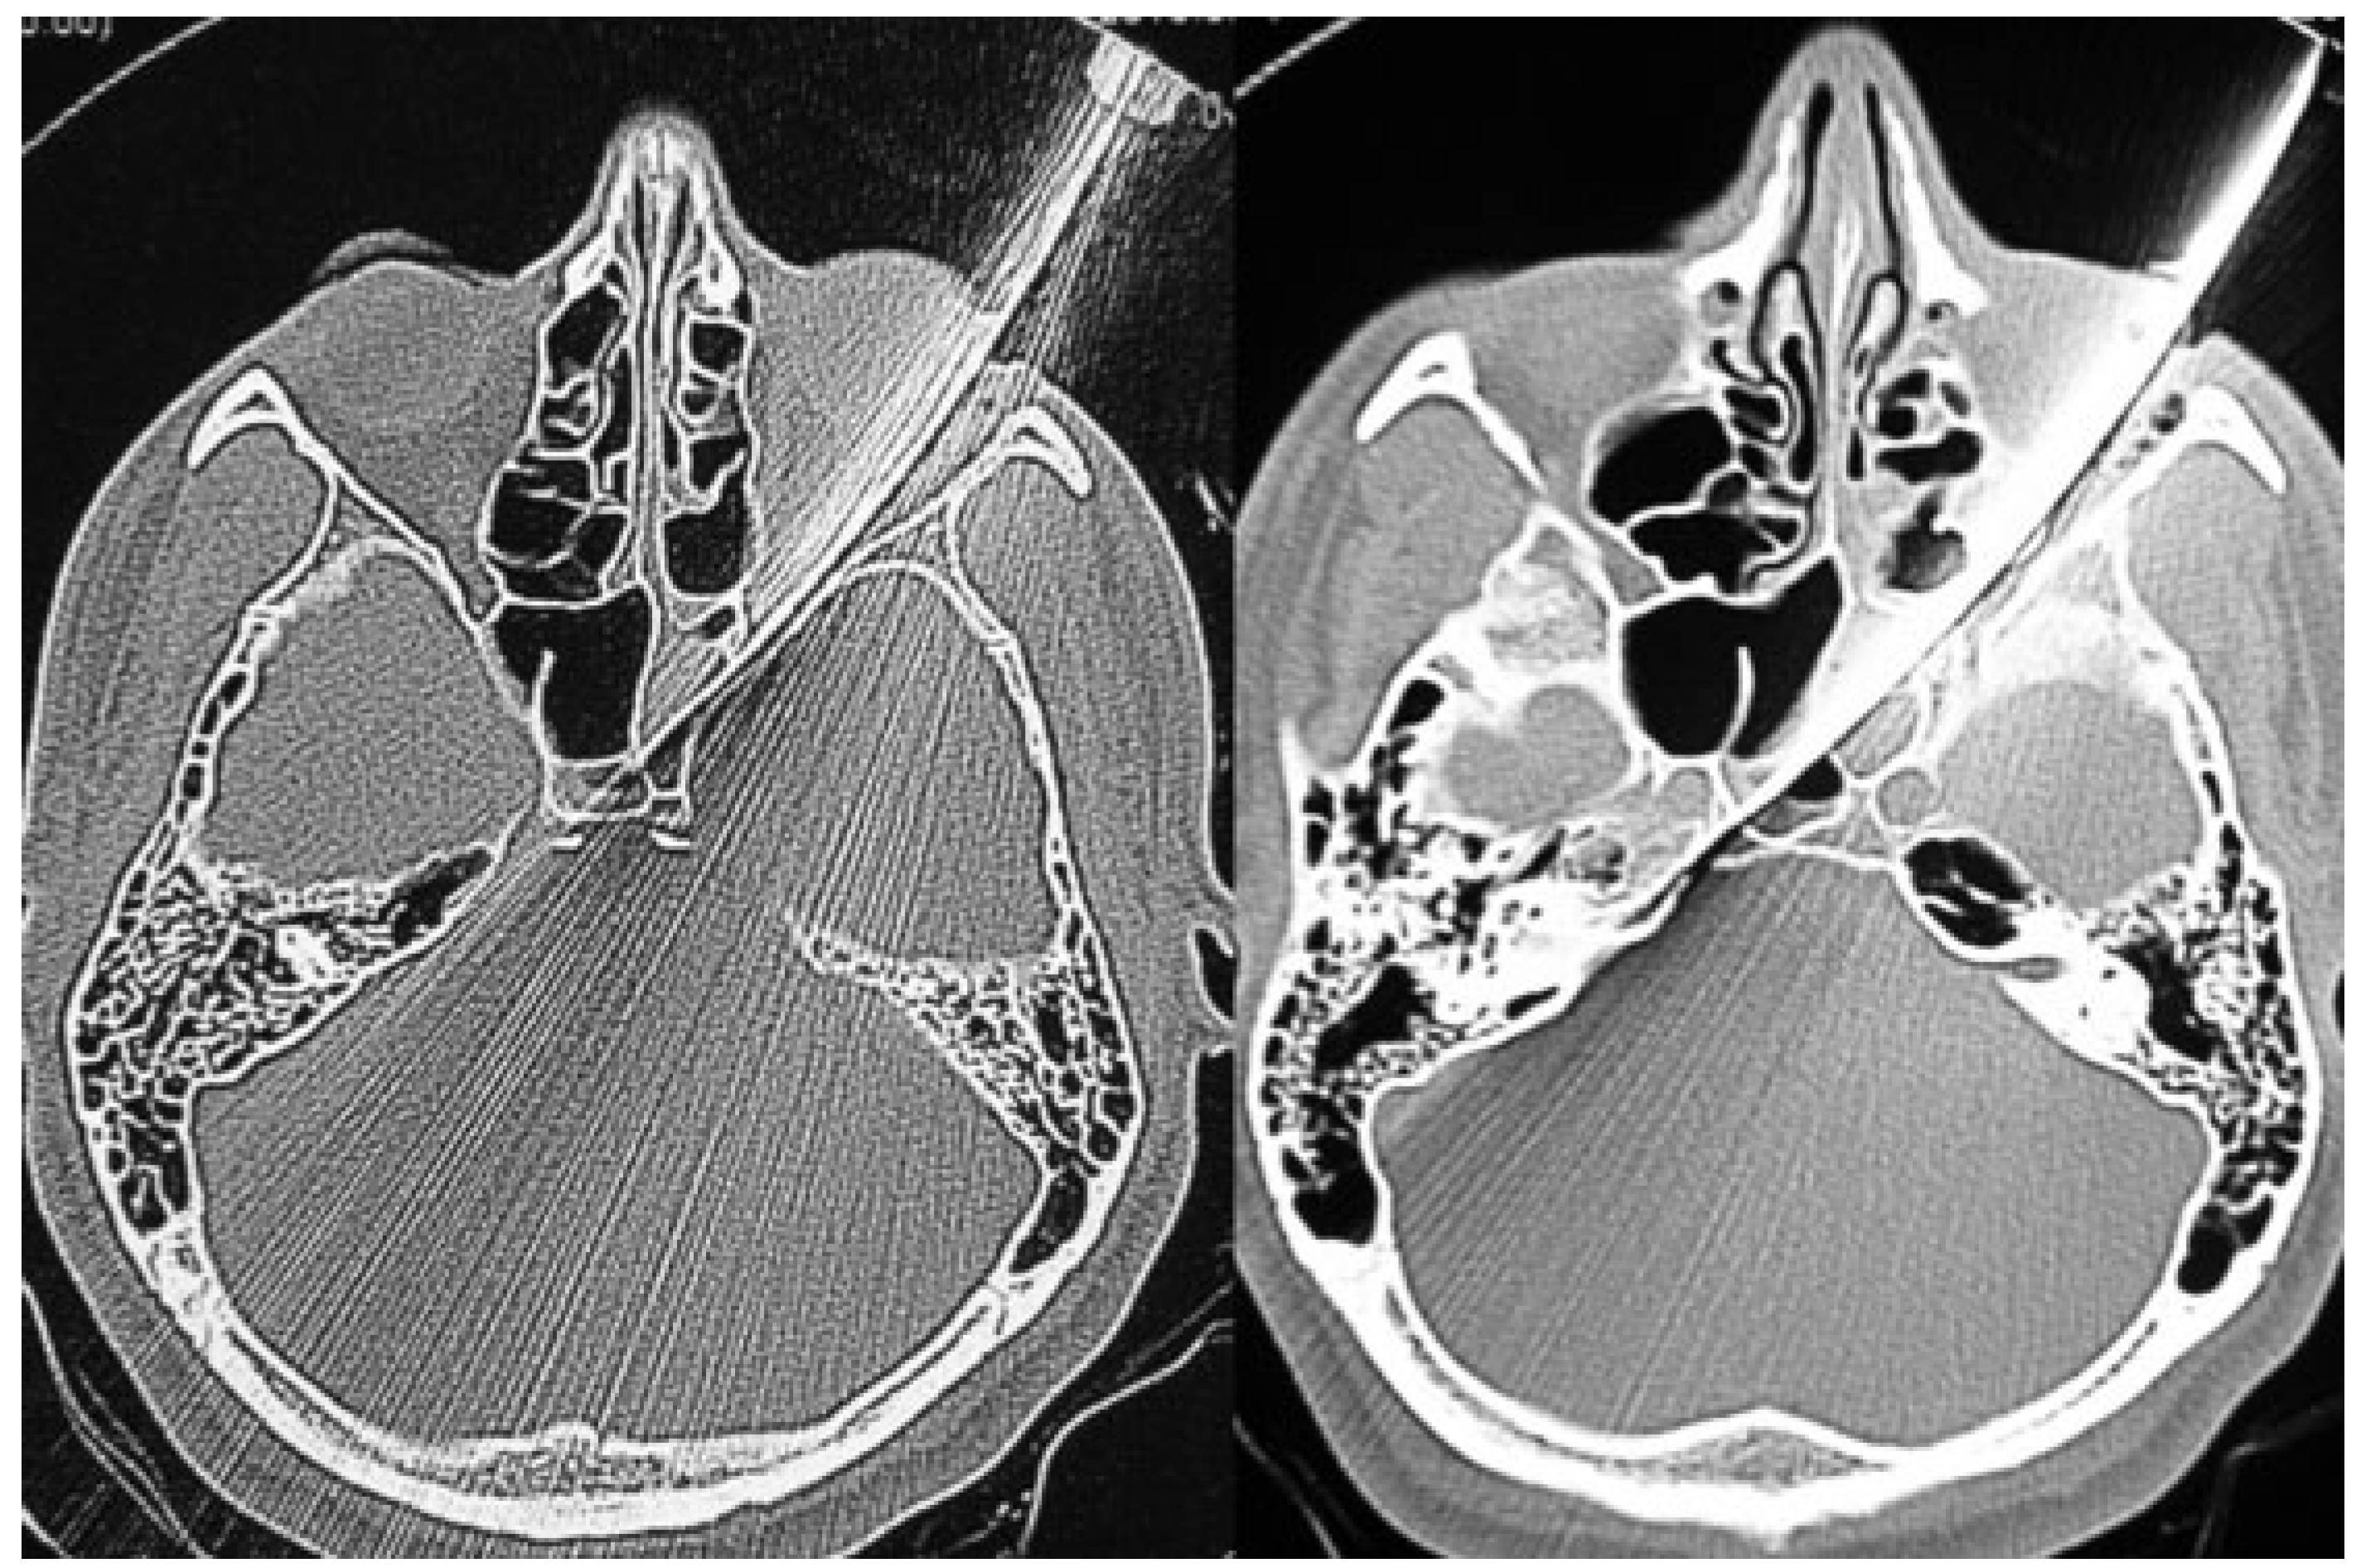

A 24-year-old man was brought to the ED by ambulance 13 h after sustaining a penetrating injury to the left orbit with a 12-cm butcher’s knife during a violent confrontation. Prehospital vital signs were BP, 110/60 mm Hg; HR, 80; RR, 22; and GCS score of 15. During primary survey at the ED, the butcher’s knife remained in situ (Figure 3) within the left orbit, vital signs were BP, 119/80 mm Hg; HR, 117; RR, 20; and GCS score of 15. Cranial CT showed the presence of the 12-cm butcher’s knife and associated left orbital fracture with penetration into the ipsilateral temporal lobe (Figure 4 and Figure 5). Six hours following arrival at the ED, the patient underwent a temporal craniotomy via a lateral orbital approach and, following ipsilateral carotid isolation, the knife was removed with minimal intraoperative bleeding (Figure 6). Six days following admission, the patient was discharged with a GOS score of 5 and normal vision in both eyes.

Figure 4.

Lateral scout view confirms the penetration of the knife into the temporal fossa.

Figure 5.

Computed tomography image demonstrating the presence of the end of the knife blade anterior to the brain stem without penetration into the posterior cranial fossa.

Figure 6.

Images of surgical intervention and removal of the knife. A left temporal approach was initiated with decompression via the removal of the lateral orbital wall and segment of temporal bone. In addition, isolation and preparation of the ipsilateral carotid artery was achieved; however, this was not used due to non vascular injury during the extraction process.